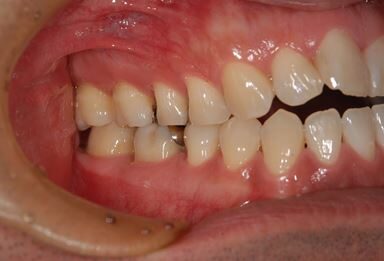

| 性別/年齢 | 男性 / 32歳 | ||||||||||||||||||||||||||||||||

| 主訴 | 銀歯がはずれたところの治療と、インプラント治療相談。 | ||||||||||||||||||||||||||||||||

| 治療方針 | 欠損部分をインプラント治療により、機能的・審美的回復を行う。 | ||||||||||||||||||||||||||||||||

| 治療内容 | インプラント2本、ハイブリッドセラミッククラウン2本 | ||||||||||||||||||||||||||||||||

| 総治療費 | 399,000円 | ||||||||||||||||||||||||||||||||

| 治療期間 | 7ヶ月 |